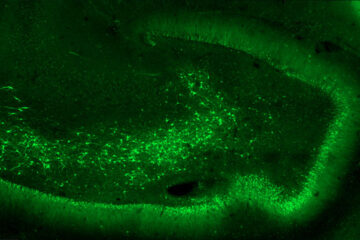

This project is based on the hypothesis that GluK2/GluK5-type kainate receptors localized ectopically at aberrant synapses formed by the sprouting of axons from dentate gyrus granule cells, act as detonators in triggering epileptic discharges in the hippocampus. In 2014, an initial study by these researchers demonstrated that the genetic deletion of grik2, the gene encoding the GluK2 subunit of the kainate-type glutamate receptors, or pharmacological inhibition of GluK2/GluK5 receptors, led to a reduction in the number of spontaneous and recurrent seizures observed in a mouse model of temporal lobe epilepsy. A patent had been filed indicating GluK2/GluK5 as a potential target for treating temporal lobe epilepsy.

In the “Annals of Neurology” article, the teams of Valérie Crépel and Christophe Mulle (and in his team the work carried out mainly by Séverine Deforges, IR CNRS), chose to develop a strategy based on interfering RNAs to reduce grik2 gene expression locally in the hippocampus. The article describes the strategy for selecting interfering RNA sequences in cell models, and the production of a viral vector that enables expression of an anti-grik2 microRNA in hippocampal neurons. This viral vector was injected in vivo into epileptic mice. The article demonstrates the efficacy of this viral vector in decreasing grik2 expression and GluK2 levels in the hippocampus, and ultimately in reducing epileptic activity in mice in vivo. Moreover, administration of the viral vector to organotypic hippocampal slices obtained from surgically resected epileptic patients, led to the suppression of epileptiform discharges recorded in these slices.